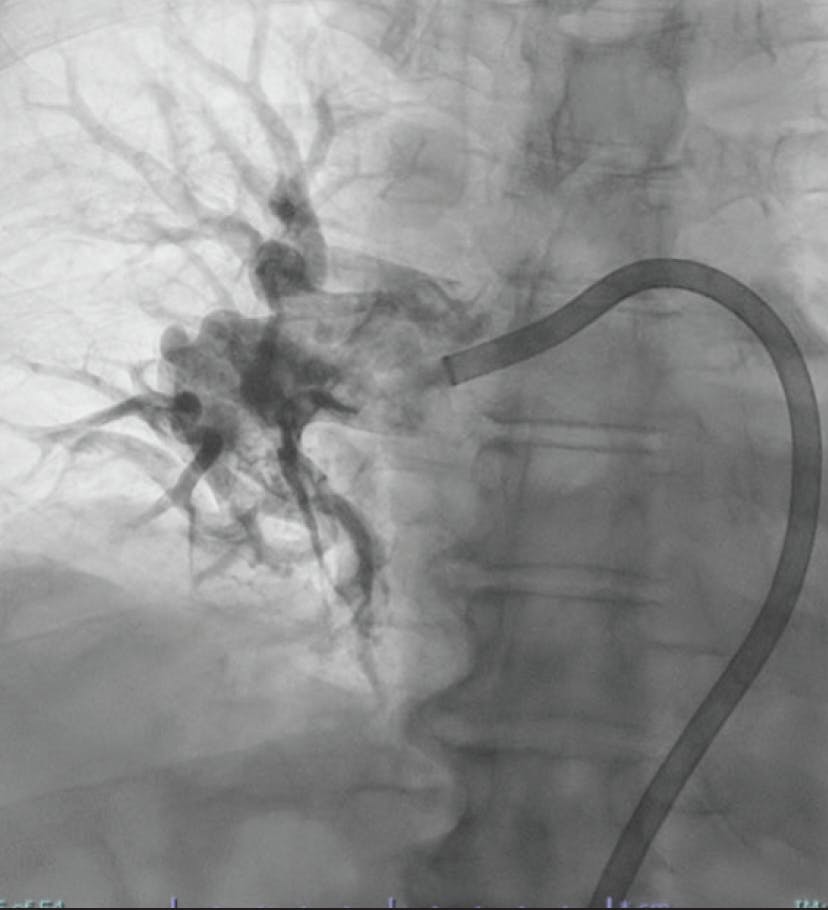

Figure 2. Angiogram depicting the Lightning Flash aspiration catheter through the Element sheath.

INTERVENTION

After gaining access in the right common femoral vein under ultrasound guidance, we selectively catheterized the PA over a 0.035-inch exchange guidewire and a 5-F pigtail catheter. We advanced into the distal, right, lower lobar PA, then exchanged the guidewire for a 1-cm, floppy-tip, 0.035-inch stiff Amplatz. Sheath exchange was performed for Penumbra’s 17-F Element sheath and dilator. Element features a HemoLock valve system, designed to ensure hemostasis, and a laser-cut hypotube design to help maintain stepwise support throughout the vasculature. Penumbra’s Lightning Flash 2.0 was inserted, and aspiration was performed in the right main, interlobar, and descending vessels, then into the upper lobar artery. The Element sheath allowed easy access to the left PA, where thrombectomy was performed in similar fashion. After 20 minutes of device time, clot was removed and reperfusion was achieved with an estimated blood loss of 150 mL.

Figure 3. Thrombus removed from the right PA.

CONCLUSION

Postprocedure, mean PA pressures decreased from 38 mm Hg to 21 mm Hg and oxygen saturation increased from 87% to 95%. The flexibility and torque-ability of the Lightning Flash 2.0 catheter paired with the foundational support of the Element sheath allowed for excellent angiographic and clinical success. Thanks to Penumbra’s VTE platform, complete with their Element sheath, we were well equipped to take on this case with confidence and perform it with ease.